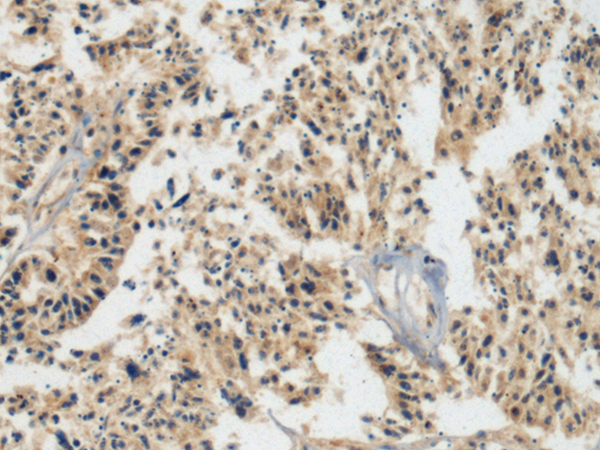

IHC 1/100-1/200 Human,Mouse,Rat